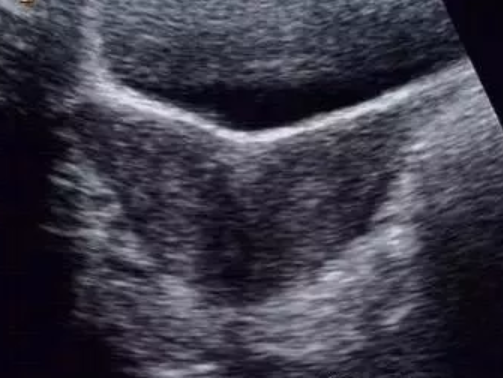

縱隔子宮、雙角子宮都是雙側(cè)副中腎管融合不良所致的畸形,在聲像上有很多相似之處,尤其是不完全縱隔子宮與雙角子宮較難鑒別,兩者主要是從子宮外形上予以區(qū)別。

雙角子宮是雙側(cè)副中腎管尾部已經(jīng)融合,末端中隔已被吸收,子宮底部融合不良,宮底較寬,兩宮角有一較深外形似羊角的凹陷,兩側(cè)各具一宮腔,雙側(cè)卵巢多正常。